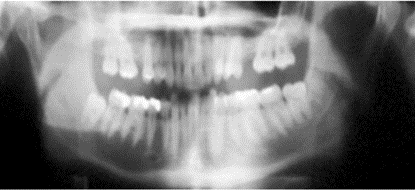

Describe what it means if the patient’s canine is behind the guide line and how this will impact the image.

Describe what it means if the patient’s canine is in front of the guide line and how this will impact the image.